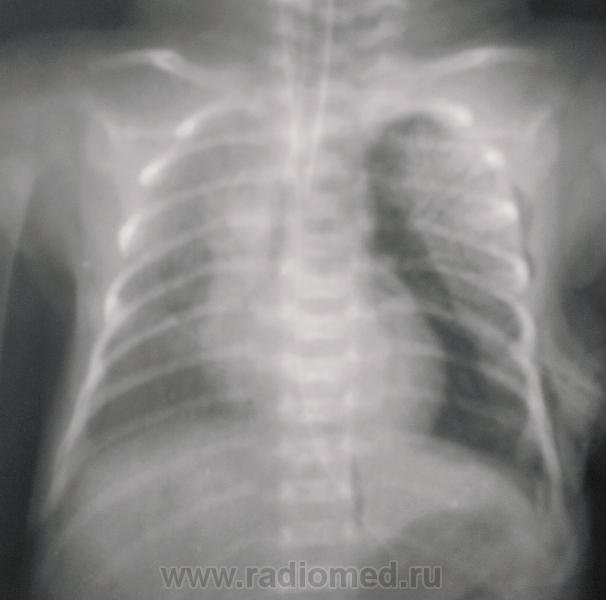

На первых снимках левосторонний пневмоторак; затем дренирование, пневмоторакс, практически, разрешился, признаки РДС  новорожденных (отек).

На последих 3-х снимках явления подкожной эмфиземы. ИМХО: смещение средостения и коллабирование лёгкого являются следствием пневаторакса, причина которого, вероятно в незрелости лёгочной ткани.

недоношенность ведь не обязательно сопровождается РДС... причины спонтанки не выяснили, запоздали с дренированием, малышка около 12 часов была с коллабированным левым легким. Думаю, что незрелость легочной паренхимы да смещение средостение с большим пневмотораксом явились причиной. Так ли?